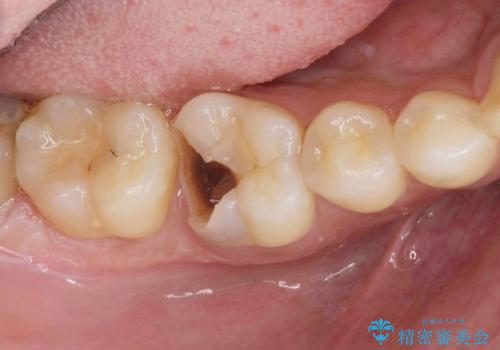

1. 放置してしまった虫歯の治療の治療前